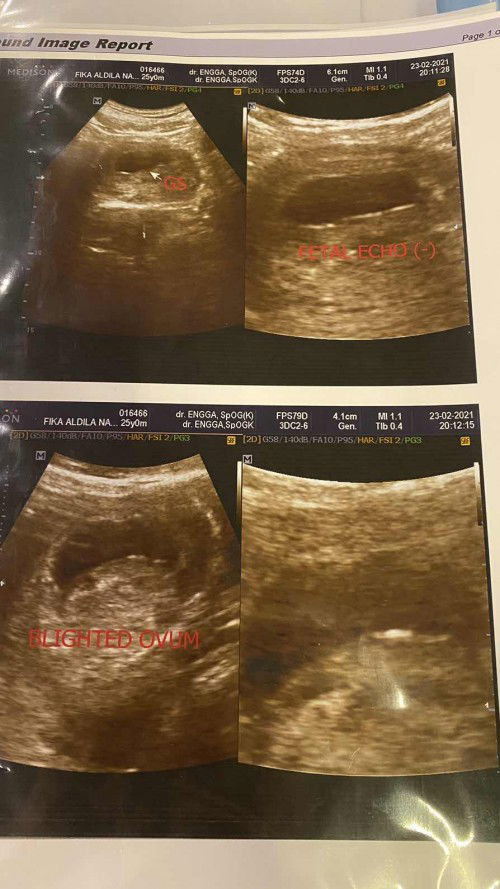

Halo bunda Hari ini saya kontrol ke dokter dan ini usg saya yg ke 4, hasil pemeriksaan nya saya di nyatakan blighted ovum. Karena djj nya negatif dan kantong hamil saya dari pemeriksaan sebelumnya mengalami penyusutan, tp selama ini belum ada flek yg keluar dan sy merasa perut saya sedikit membesar, kalau di hitung dari hpht umur kehamilan saya sudah 10 minggu. Saya disarankan minum obat untuk menggugurkan kandungan saya, tp saya masih takut. Apakah ada yg pernah mengalami hal yg sama ? Saran dan masukan nya bund 🥺#ingintahu #firstbaby